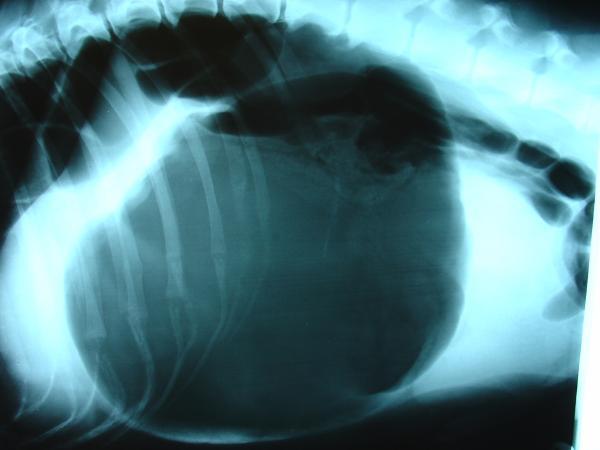

Também se costumam fazer radiografias para confirmar este diagnóstico. A radiografia permite ver com clareza se o estômago está distendido ou não. Além disso, se o estômago tiver rodado, o piloro (orifício que conecta o estômago com o intestino) fica deslocado em relação à sua posição normal.